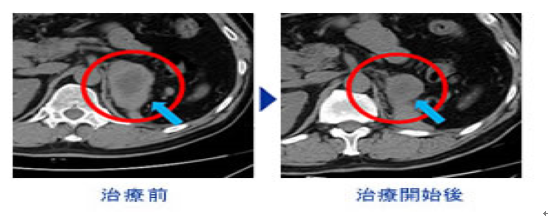

NK细胞治疗 免疫抗癌剂 肝癌治疗有效果?!

前面也有提到过NK细胞在人体血液中.首先要进行採血.在血液中提取NK细胞.在和opdivo+yervoy抗癌剂(压制癌细胞 不再扩大)等.进行培养后.将培养出来的免疫细胞注射体内.

NK细胞的活性度提高.可杀伤任何癌细胞.

有效去除手术 放射线治疗后残留的 细小癌症.